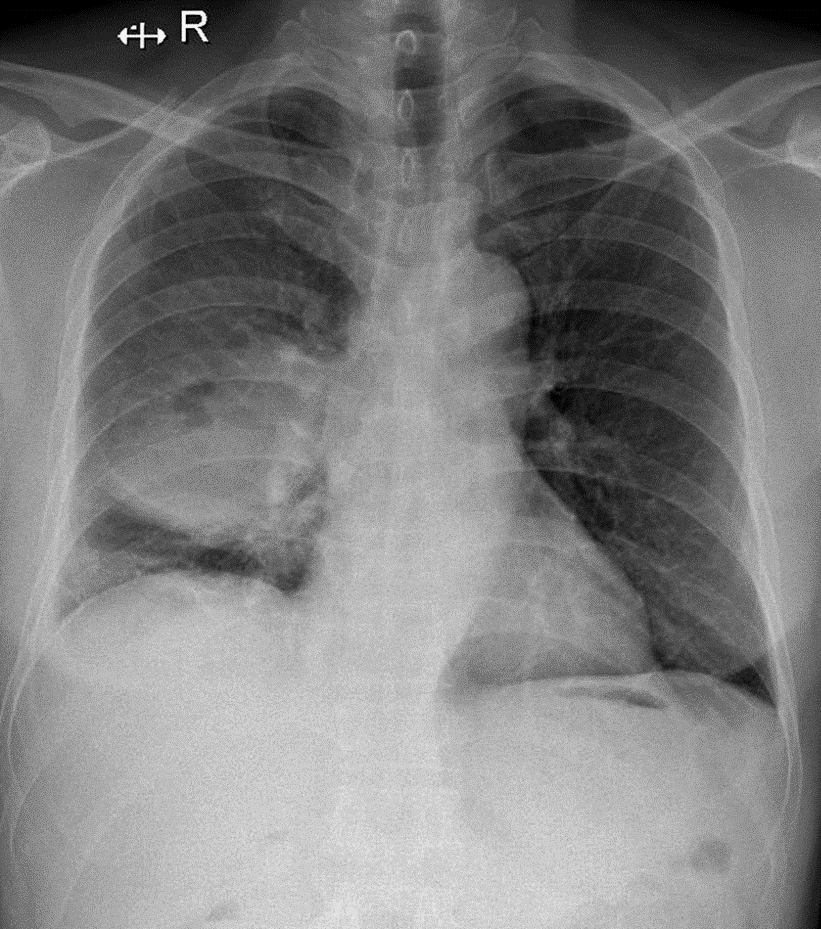

Hãy phân tích tình huống Nam 62 tuổi

1-Tổn thương dạng khối mờ vùng rốn phổi (P) => U phổi 2-Tràn dịch màng phổi (P)